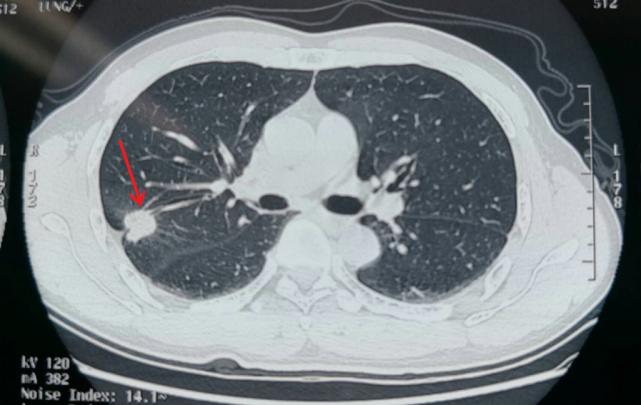

CT发现肺部小癌灶

CT的强项在于能够敏感地看到肺部是不是有问题,问题在哪里,大致是什么性质的问题,漏诊比较少。但在具体病灶性质的细节方面还有缺陷,最权威的专家也不敢说绝对不会出现误诊。

CT对肺部病变的显示非常敏感